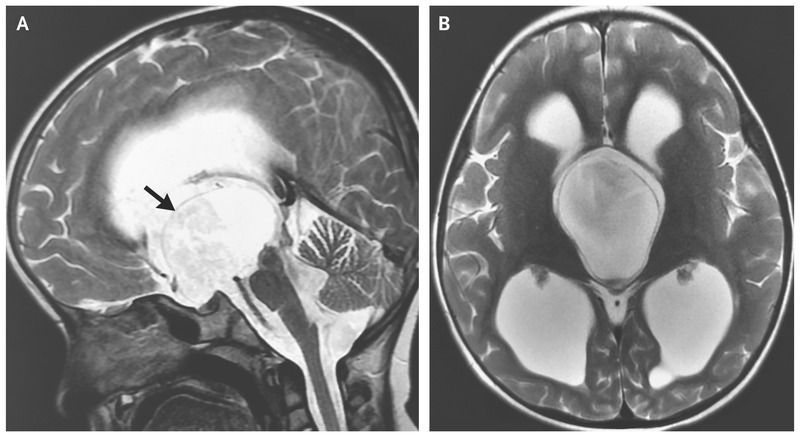

A 5-year-old girl presented to the pediatric neurosurgery clinic with a 2-year history of excessive head nodding. On examination, she was alert, with normal cognitive function. She displayed continuous, rhythmic, anteroposterior head-bobbing movements at a frequency of 2 to 3 Hz. The movements diminished in intensity when she engaged in volitional activity, such as talking. Magnetic resonance imaging of the head showed a well-defined, thin-walled, suprasellar cystic lesion (Panel A, arrow). The lesion caused obstruction at the foramina of Monro or at the third ventricle, with resulting ventriculomegaly (Panel B). A diagnosis of a suprasellar arachnoid cyst with bobblehead-doll syndrome was made. This is a rare pediatric movement disorder characterized by continuous or episodic involuntary head nodding at a frequency of 2 to 3 Hz. The movements stop during sleep and may disappear or attenuate with volitional activity. The syndrome is associated with cystic abnormalities in the region of the anterior third ventricle. The patient underwent endoscopic cystoventriculostomy and cystocisternostomy for the suprasellar arachnoid cyst. At follow-up 6 weeks after the procedure, she had partial resolution of her symptoms, with a reduction in both the frequency and intensity of head movements.